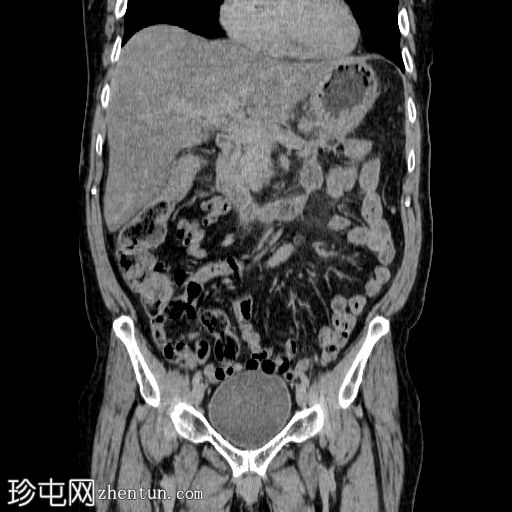

冠状面

非造影

胰体尾弥漫性增大,特征为胰腺实质低强化,无明显坏死区域。

该病灶与以下表现相关:

胰周筋膜平面边界不清的污迹,无明显壁形成、气室、固体碎片或血液产物。

多个亚厘米大小、非特异性的腹主动脉旁淋巴结和肠系膜淋巴结,可能具有反应性。

病变范围如下:

病变横向延伸至左前肾旁间隙,伴有Gerota筋膜增厚。

病变向下延伸至盆腔。

无肠系膜或脾脏血管阻塞的证据。

未见导管扩张或钙化。